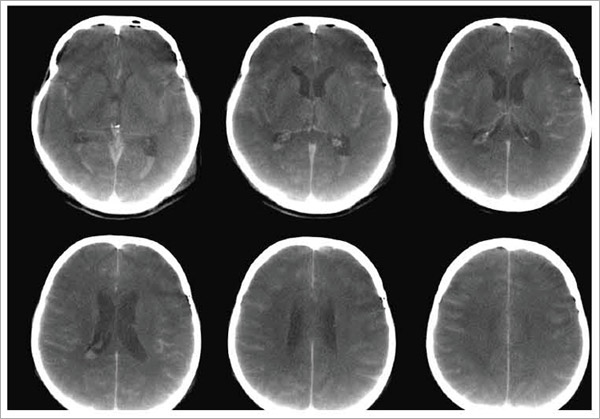

図1 クモ膜下出血(造影)

DynaCT/DAによるMPR(アキシャル像)